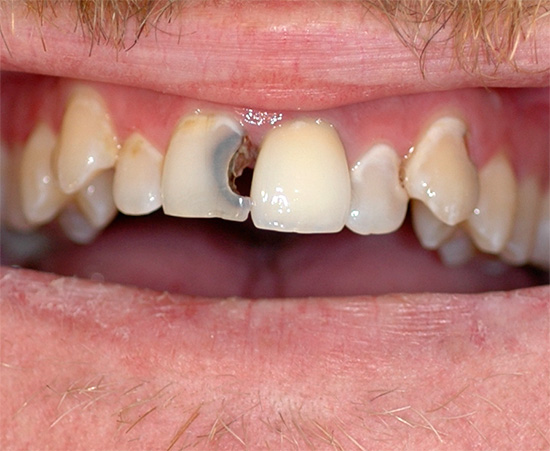

Mas na maioria das vezes os dentes doem devido a várias patologias: devido a cárie profunda, pulpite ou periodontite, e nesses casos a dor pode variar de leve e rápida a muito aguda e constante. Além disso, também pode ser observado inchaço das gengivas e bochechas (edema), febre, dor de cabeça e outros sintomas desagradáveis.

- Cárie, que em diferentes estágios pode se manifestar como dor fraca e que passa rapidamente, e dor bastante forte. Se você suprimir essa dor de dente em casa com pílulas, o processo de cárie inevitavelmente chegará à polpa, resultando em pulpite - e essa é uma dor muito mais intensa, e o tratamento desse dente estará associado à necessidade de remover o "nervo" dele. Geralmente, esse é um procedimento longo e caro, especialmente no caso de dentes multicanais.